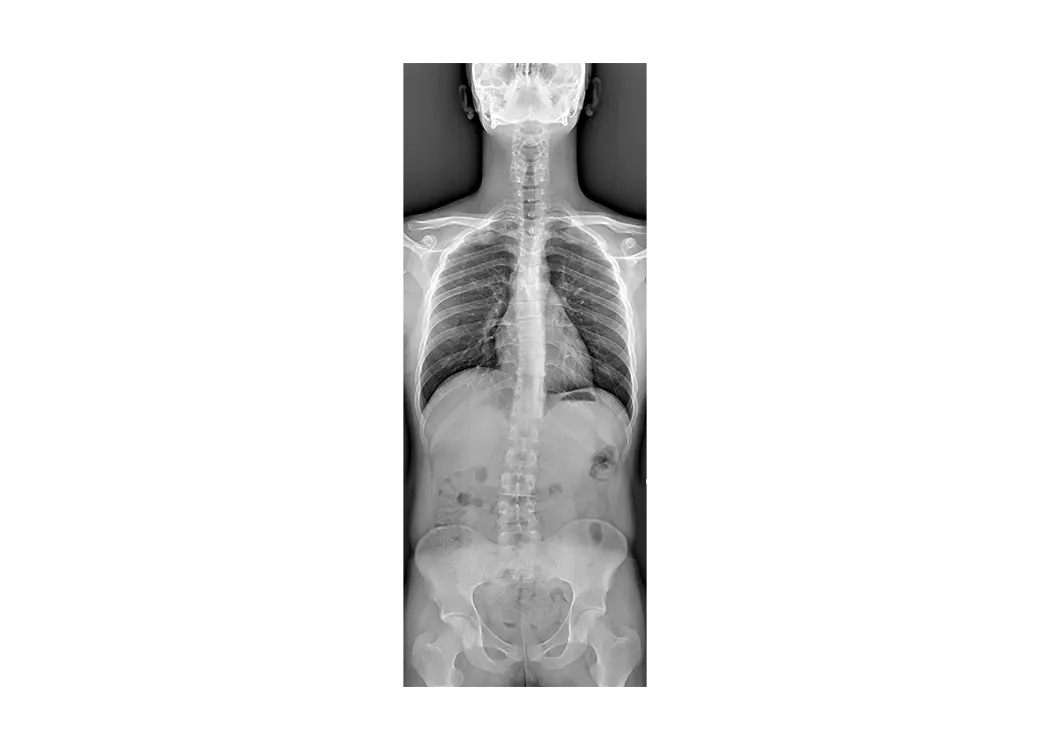

Le suivi du tube-détecteur assure des mouvements parfaitement synchronisés entre le détecteur numérique et le tube à rayons X, tout en maintenant un alignement parfait, même en cas de projections latérales. Les grandes dimensions du plateau et la couverture étendue du sélecteur motorisé dans les plans longitudinal et latéral garantissent que même les patients de grande taille peuvent être couverts de la tête aux pieds sans avoir besoin de les déplacer.

Le mouvement automatique et synchronisé du tube RX et du détecteur permet la reconstruction de longs segments squelettiques, ce qui permet d’obtenir une image unique et parfaite. Le mode Stitching est disponible à la fois dans le sens horizontal et vertical, ce qui permet de s’adapter à différentes positions du patient.